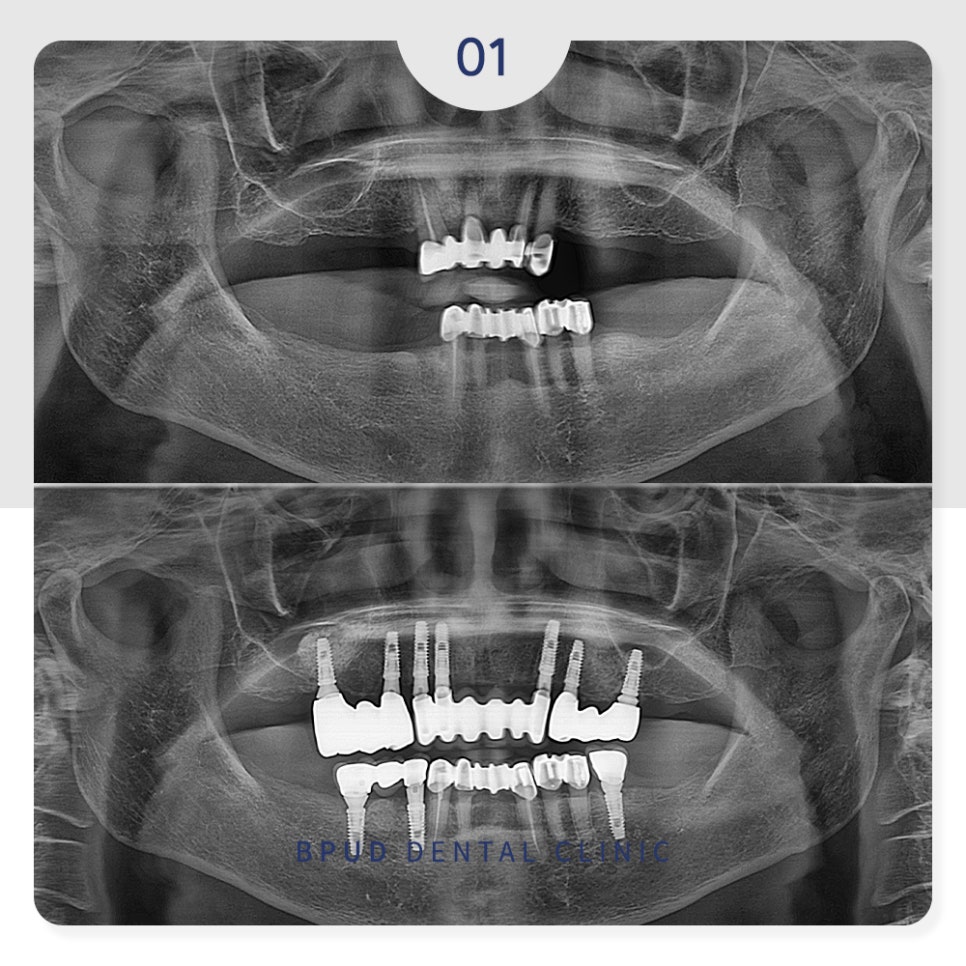

먼저 위쪽에 남아있던 치아들은

심한 우식과 치주염으로 상태가 좋지 않아

전체 발치 후 7개의 임플란트를 식립하였고

아래쪽은 남아있는 치아를 보존하여

필요한 만큼의 임플란트만 식립을 하였습니다.

그와 동시에, 위쪽은 부족한 부분의 뼈이식을 위해

오른쪽은 측방 접근법을 통한 상악동 거상술,

왼쪽은 치조정 접근법을 통한 거상술을 시행하였습니다.

최종 보철물까지 완료한 모습입니다.